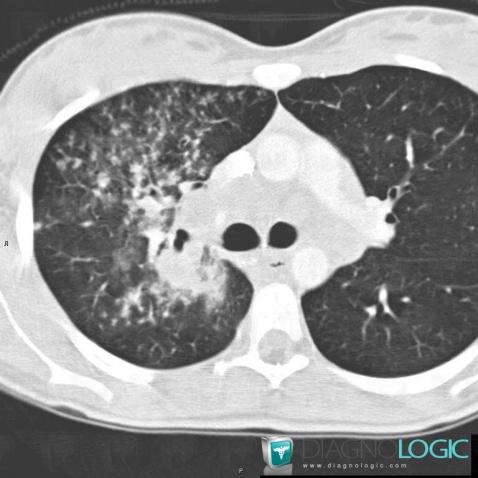

Voici les informations spécifiques à l'image clé ci dessus:

- Diagnostic Tuberculose , Localisation(s) Parenchyme pulmonaire, comportant les gammes Micronodules centrolobulaires pulmonaires

Voici les informations spécifiques à l'image clé ci dessus:

- Diagnostic Tuberculose , Localisation(s) Parenchyme pulmonaire, comportant les gammes Micronodules centrolobulaires pulmonaires